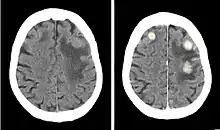

Contrast CT of a patient with brain metastases from breast cancer, before (left) and after (right) injection of an iodine-containing contrast agent

Iopentol is an iodine-containing, water-soluble radiocontrast agent. The iodine atoms readily absorb X-rays, resulting in a higher contrast of X-ray images. It has a low osmolality, meaning that the solution has a relatively low concentration of molecules; this is usually associated with fewer adverse effects than high-osmolality contrast agents.[1][2]